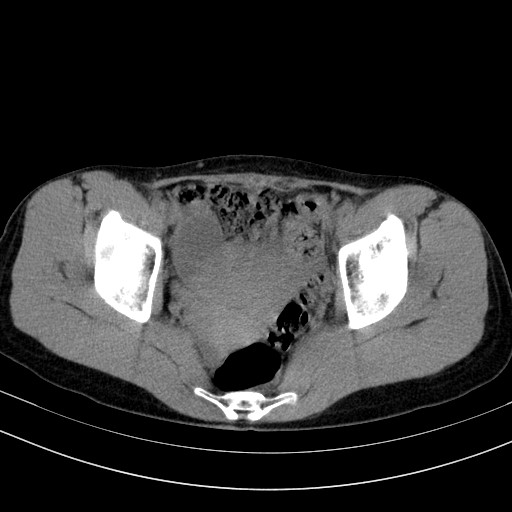

以下是引用卜一在2009-4-7 5:08:00的发言:[br]宫颈癌可能。支持!

以下是引用随光逐影在2009-4-7 8:17:00的发言:[br]考虑宫颈占位性病变(宫颈癌?);建议行进一步检查。

以下是引用jiangjing在2009-4-7 16:46:00的发言:[br]宫颈增大,结构不清,右侧附件区可疑囊样占位,建议增强及mri 检查